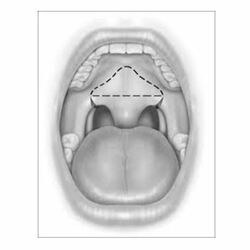

Tonsillectomy is a surgical procedure in which both palatine tonsils are fully removed from the back of the throat.

UPPP

Uvulopalatopharyngoplasty (UPPP) is a surgical procedure to eliminate extra tissues. This procedure increases the oropharyngeal airspace by resecting tissue in the throat, including one or more of the following:

- The uvula the soft flap that hangs down at the back of the throat.

- Parts of the soft palate and tissue at the side of the throat.

- Tonsils and adenoids in the even they are present.